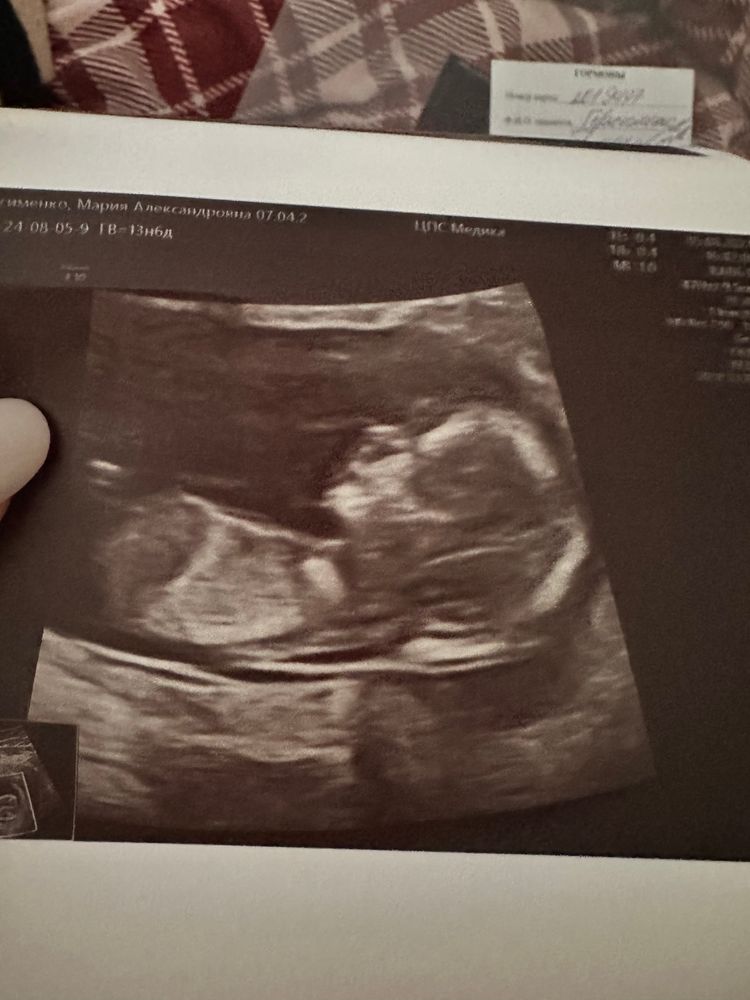

Ирина, Изображение

17.09.2024

Ирина,